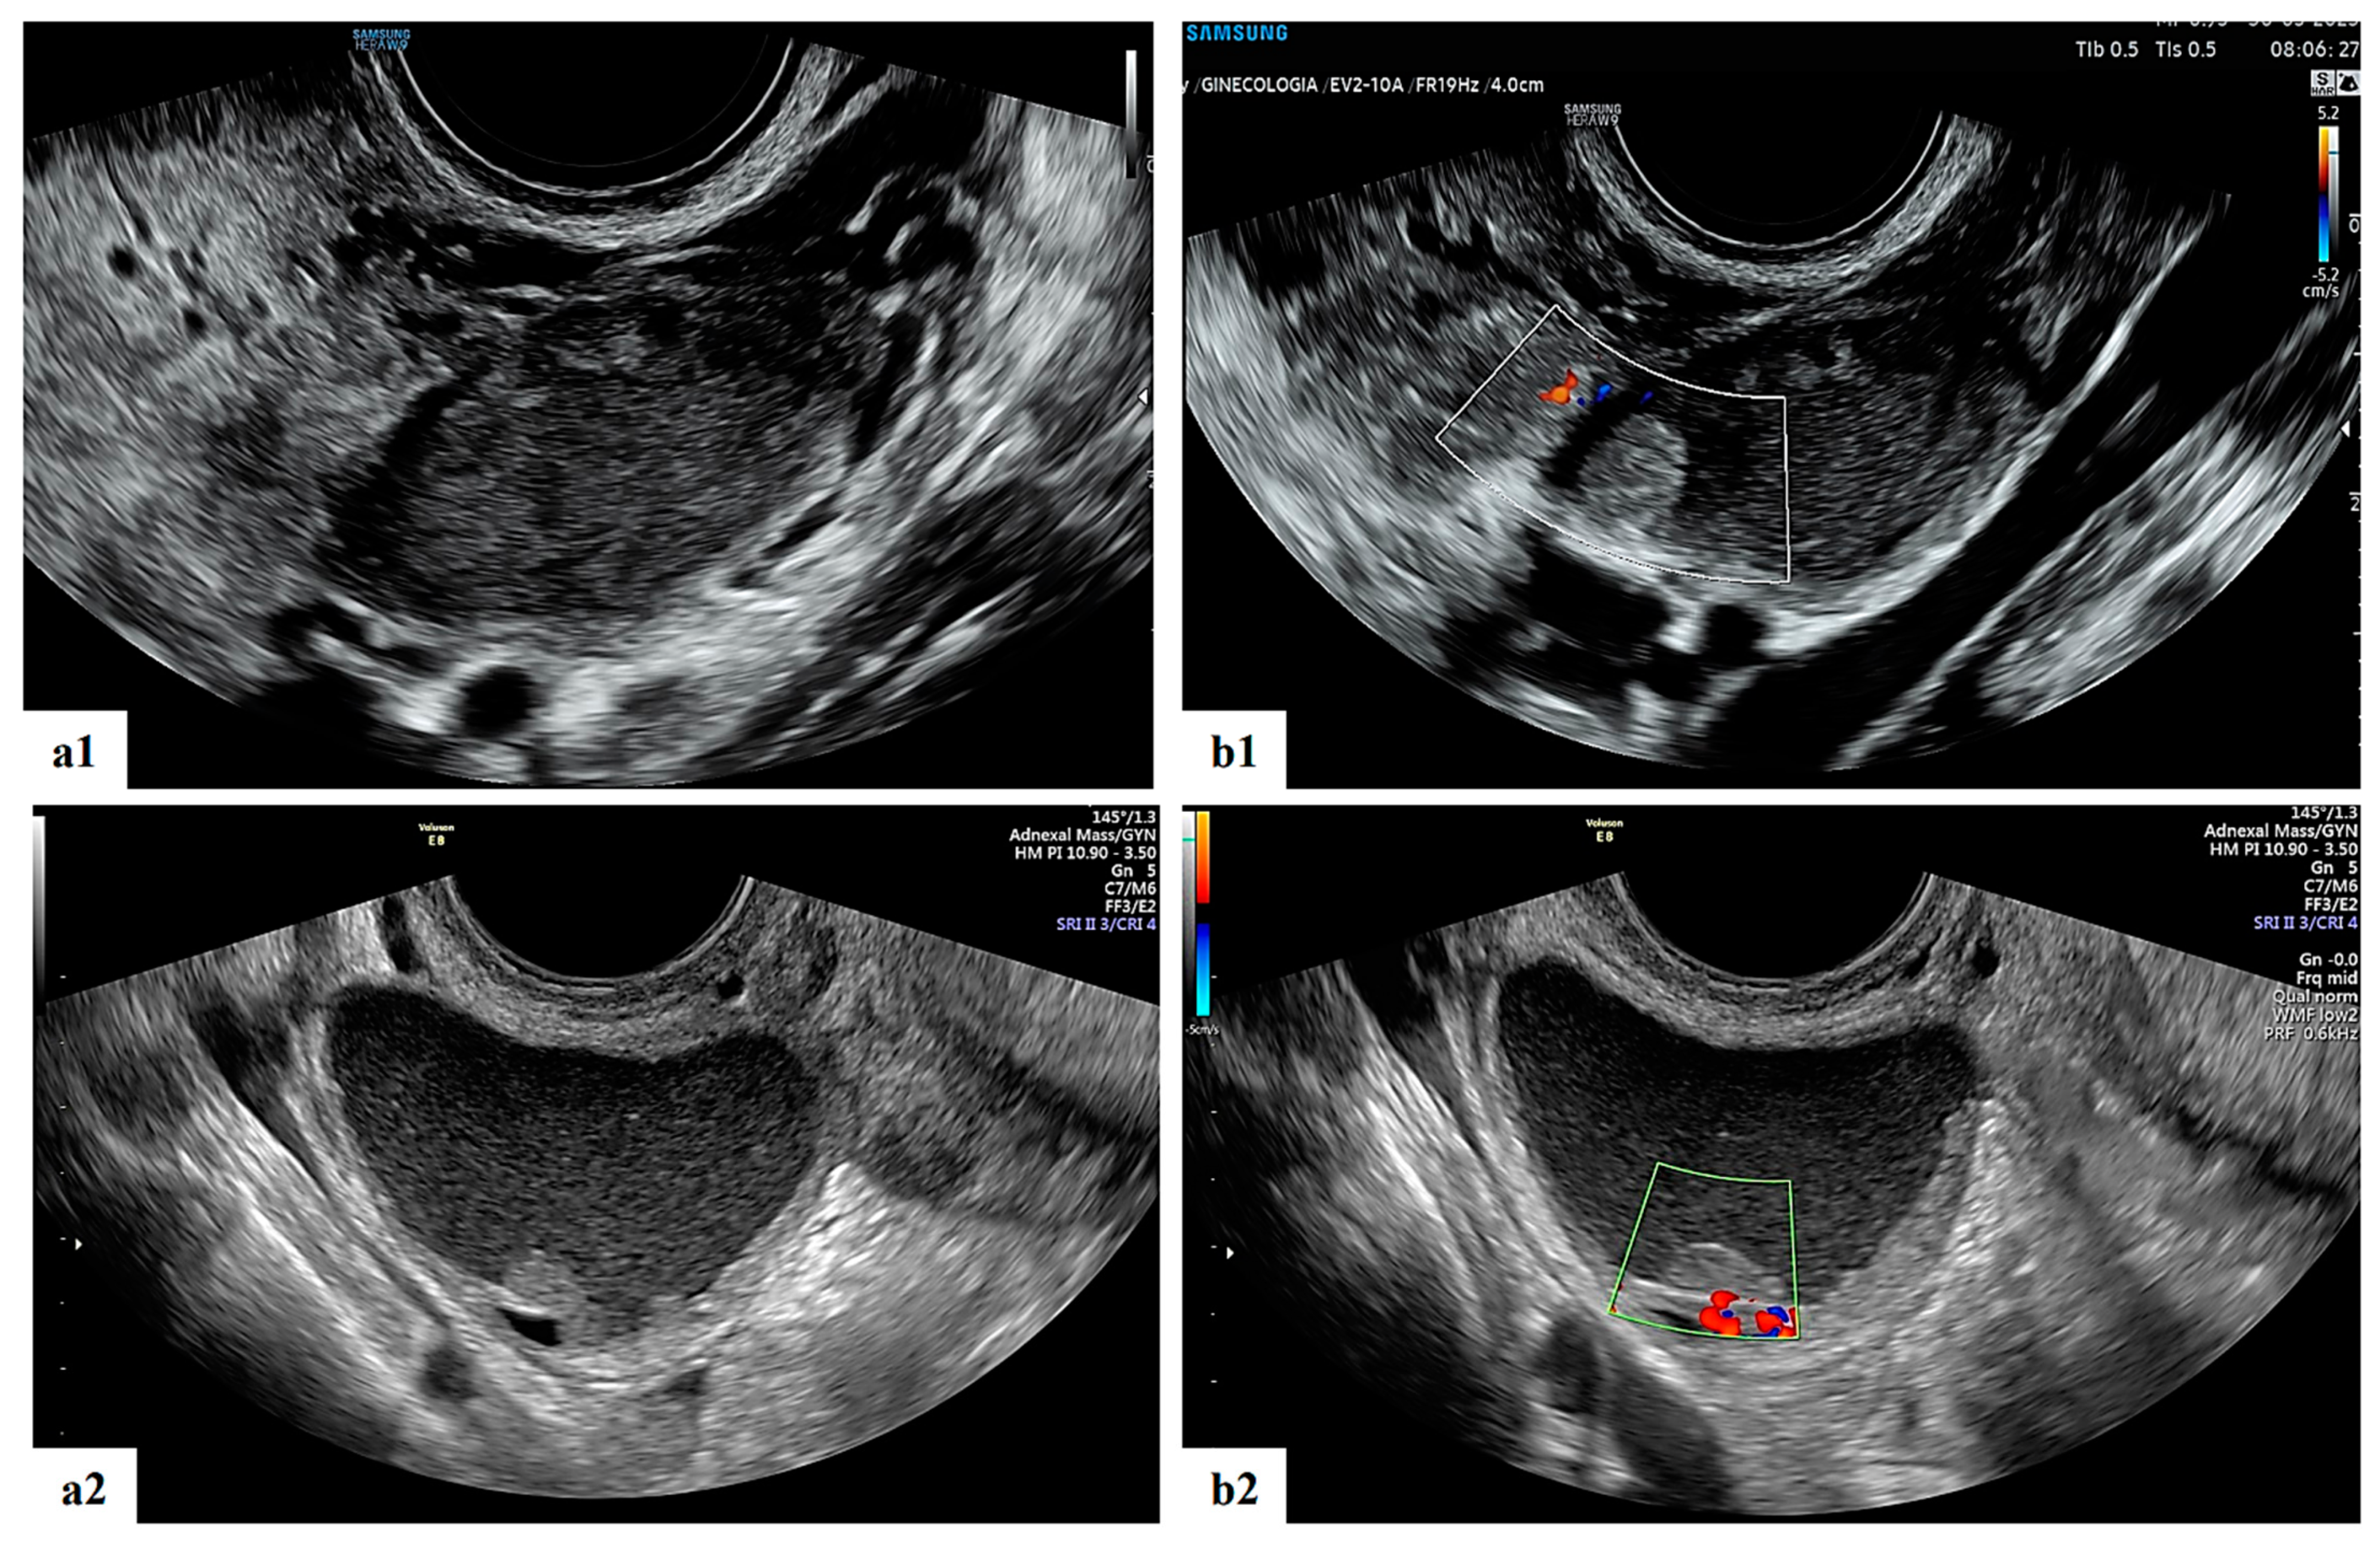

- Mascilini, F.; Moruzzi, C.; Giansiracusa, C.; Guastafierro, F.; Savelli, L.; De Meis, L.; Epstein, E.; Timor-Tritsch, I.E.; Mailath-Pokorny, M.; Ercoli, A.; et al. Imaging in gynecological disease. 10: Clinical and ultrasound characteristics of decidualized endometriomas surgically removed during pregnancy. Ultrasound Obstet. Gynecol. 2014, 44, 354–360. [Google Scholar] [CrossRef]

- Pateman, K.; Moro, F.; Mavrelos, D.; Foo, X.; Hoo, W.L.; Jurkovic, D. Natural history of ovarian endometrioma in pregnancy. BMC Women’s Health 2014, 14, 128. [Google Scholar] [CrossRef]